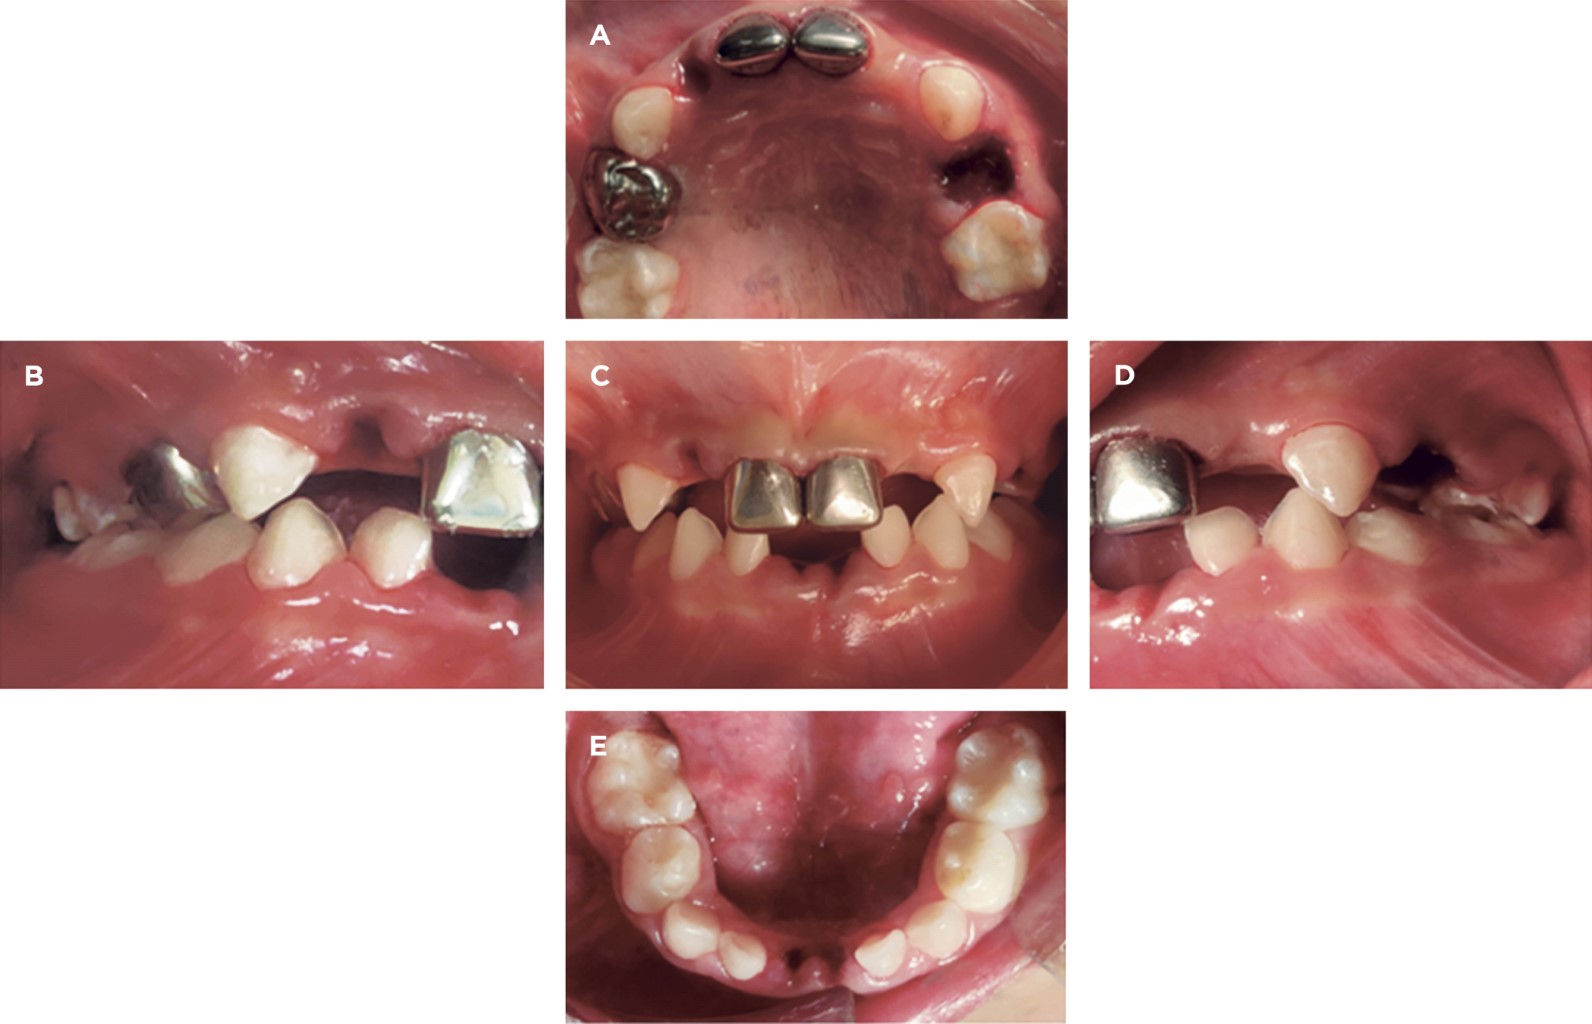

Posteriormente, debido a la nula cooperación de la paciente, edad, extensión del tratamiento especializado, así como por sus patologías de base, se elige efectuar la rehabilitación bucal bajo anestesia general (RBBAG) previa valoración preanestésica y profilaxis antiendocarditis infecciosa con una cefalosporina de tercera generación (Figura 2).

Se realizó un total de 13 tratamientos en 1 hora y 55 minutos, de los cuales cuatro fueron extracciones, tres colocaciones de coronas níquel-cromo y seis restauraciones con giómeros (Figura 3).